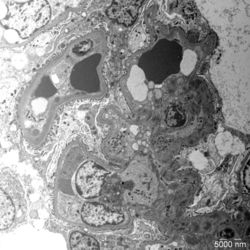

- Figure 4: Electron microscopy image of glomerular lesions in a patient with C3 glomerulopathy